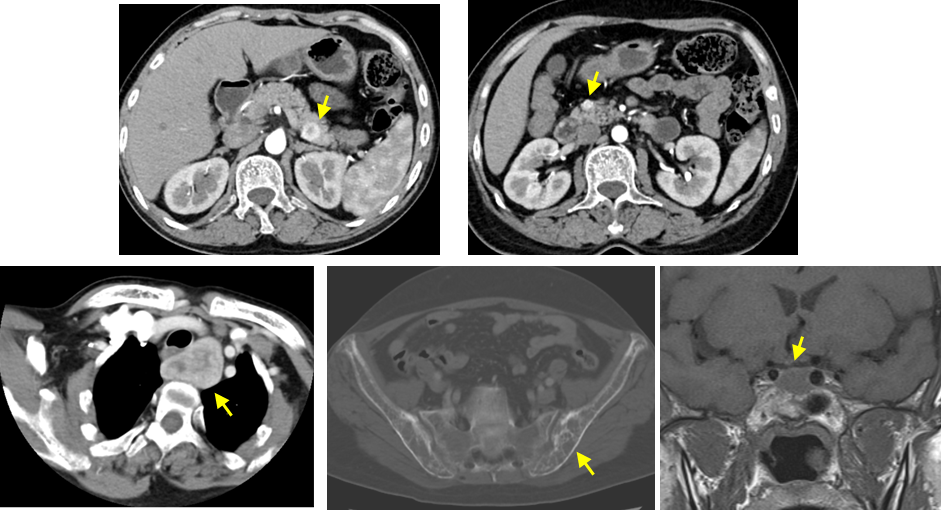

图9 全胰腺浆液性囊腺瘤(SCN)—VHL综合征

(图片来源:余日胜教授讲课使用)

图10 MENⅠ型 F/45 甲状旁腺瘤、胰腺多发神经内分泌肿瘤(pNENs)、垂体瘤